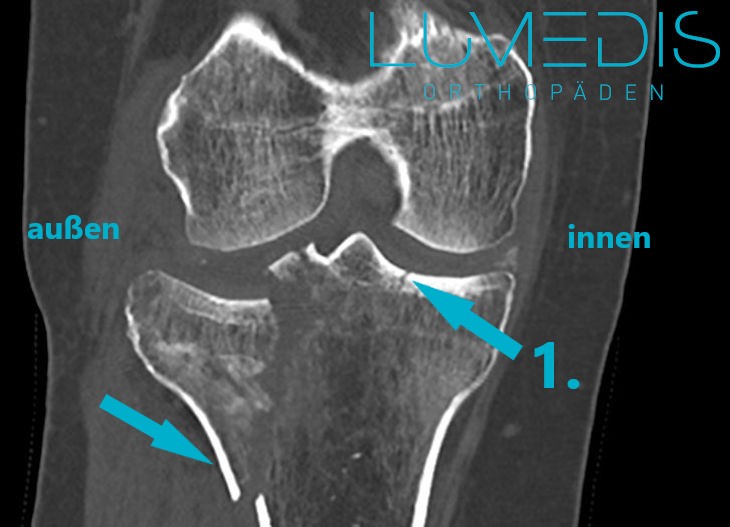

CT-Rekonstruktion einer Tibiakopffraktur links

MRT einer rechten lateralen Tibiakopffraktur

Die Pfeile zeigen auf die verschiedenen Frakturlinien im Tibiakopf.

CT einer rechten lateralen Tibiakopffraktur